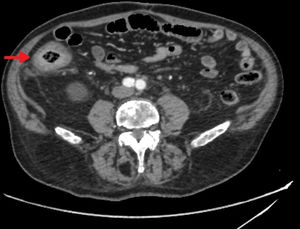

Varón de 87 años, en seguimiento en oncología por antecedentes de GIST gástrico intervenido. En la TC de control se objetivó engrosamiento mural concéntrico en colon ascendente (fig. 1). Se completó el estudio con colonoscopia donde se observó lesión de aspecto ulcerado y circunferencial a nivel de ciego (fig. 2). El estudio anatomopatológico reveló la presencia de células ovaladas con núcleos redondeados centrales y citoplasma metacromático compatibles con mastocitos, que infiltraban la lámina propia y que presentaban inmunorreactividad CD-117 (fig. 3). A pesar de estos hallazgos, y debido a la enfermedad basal del paciente, se decidió no continuar estudio de mastocitosis sistémica (MS).